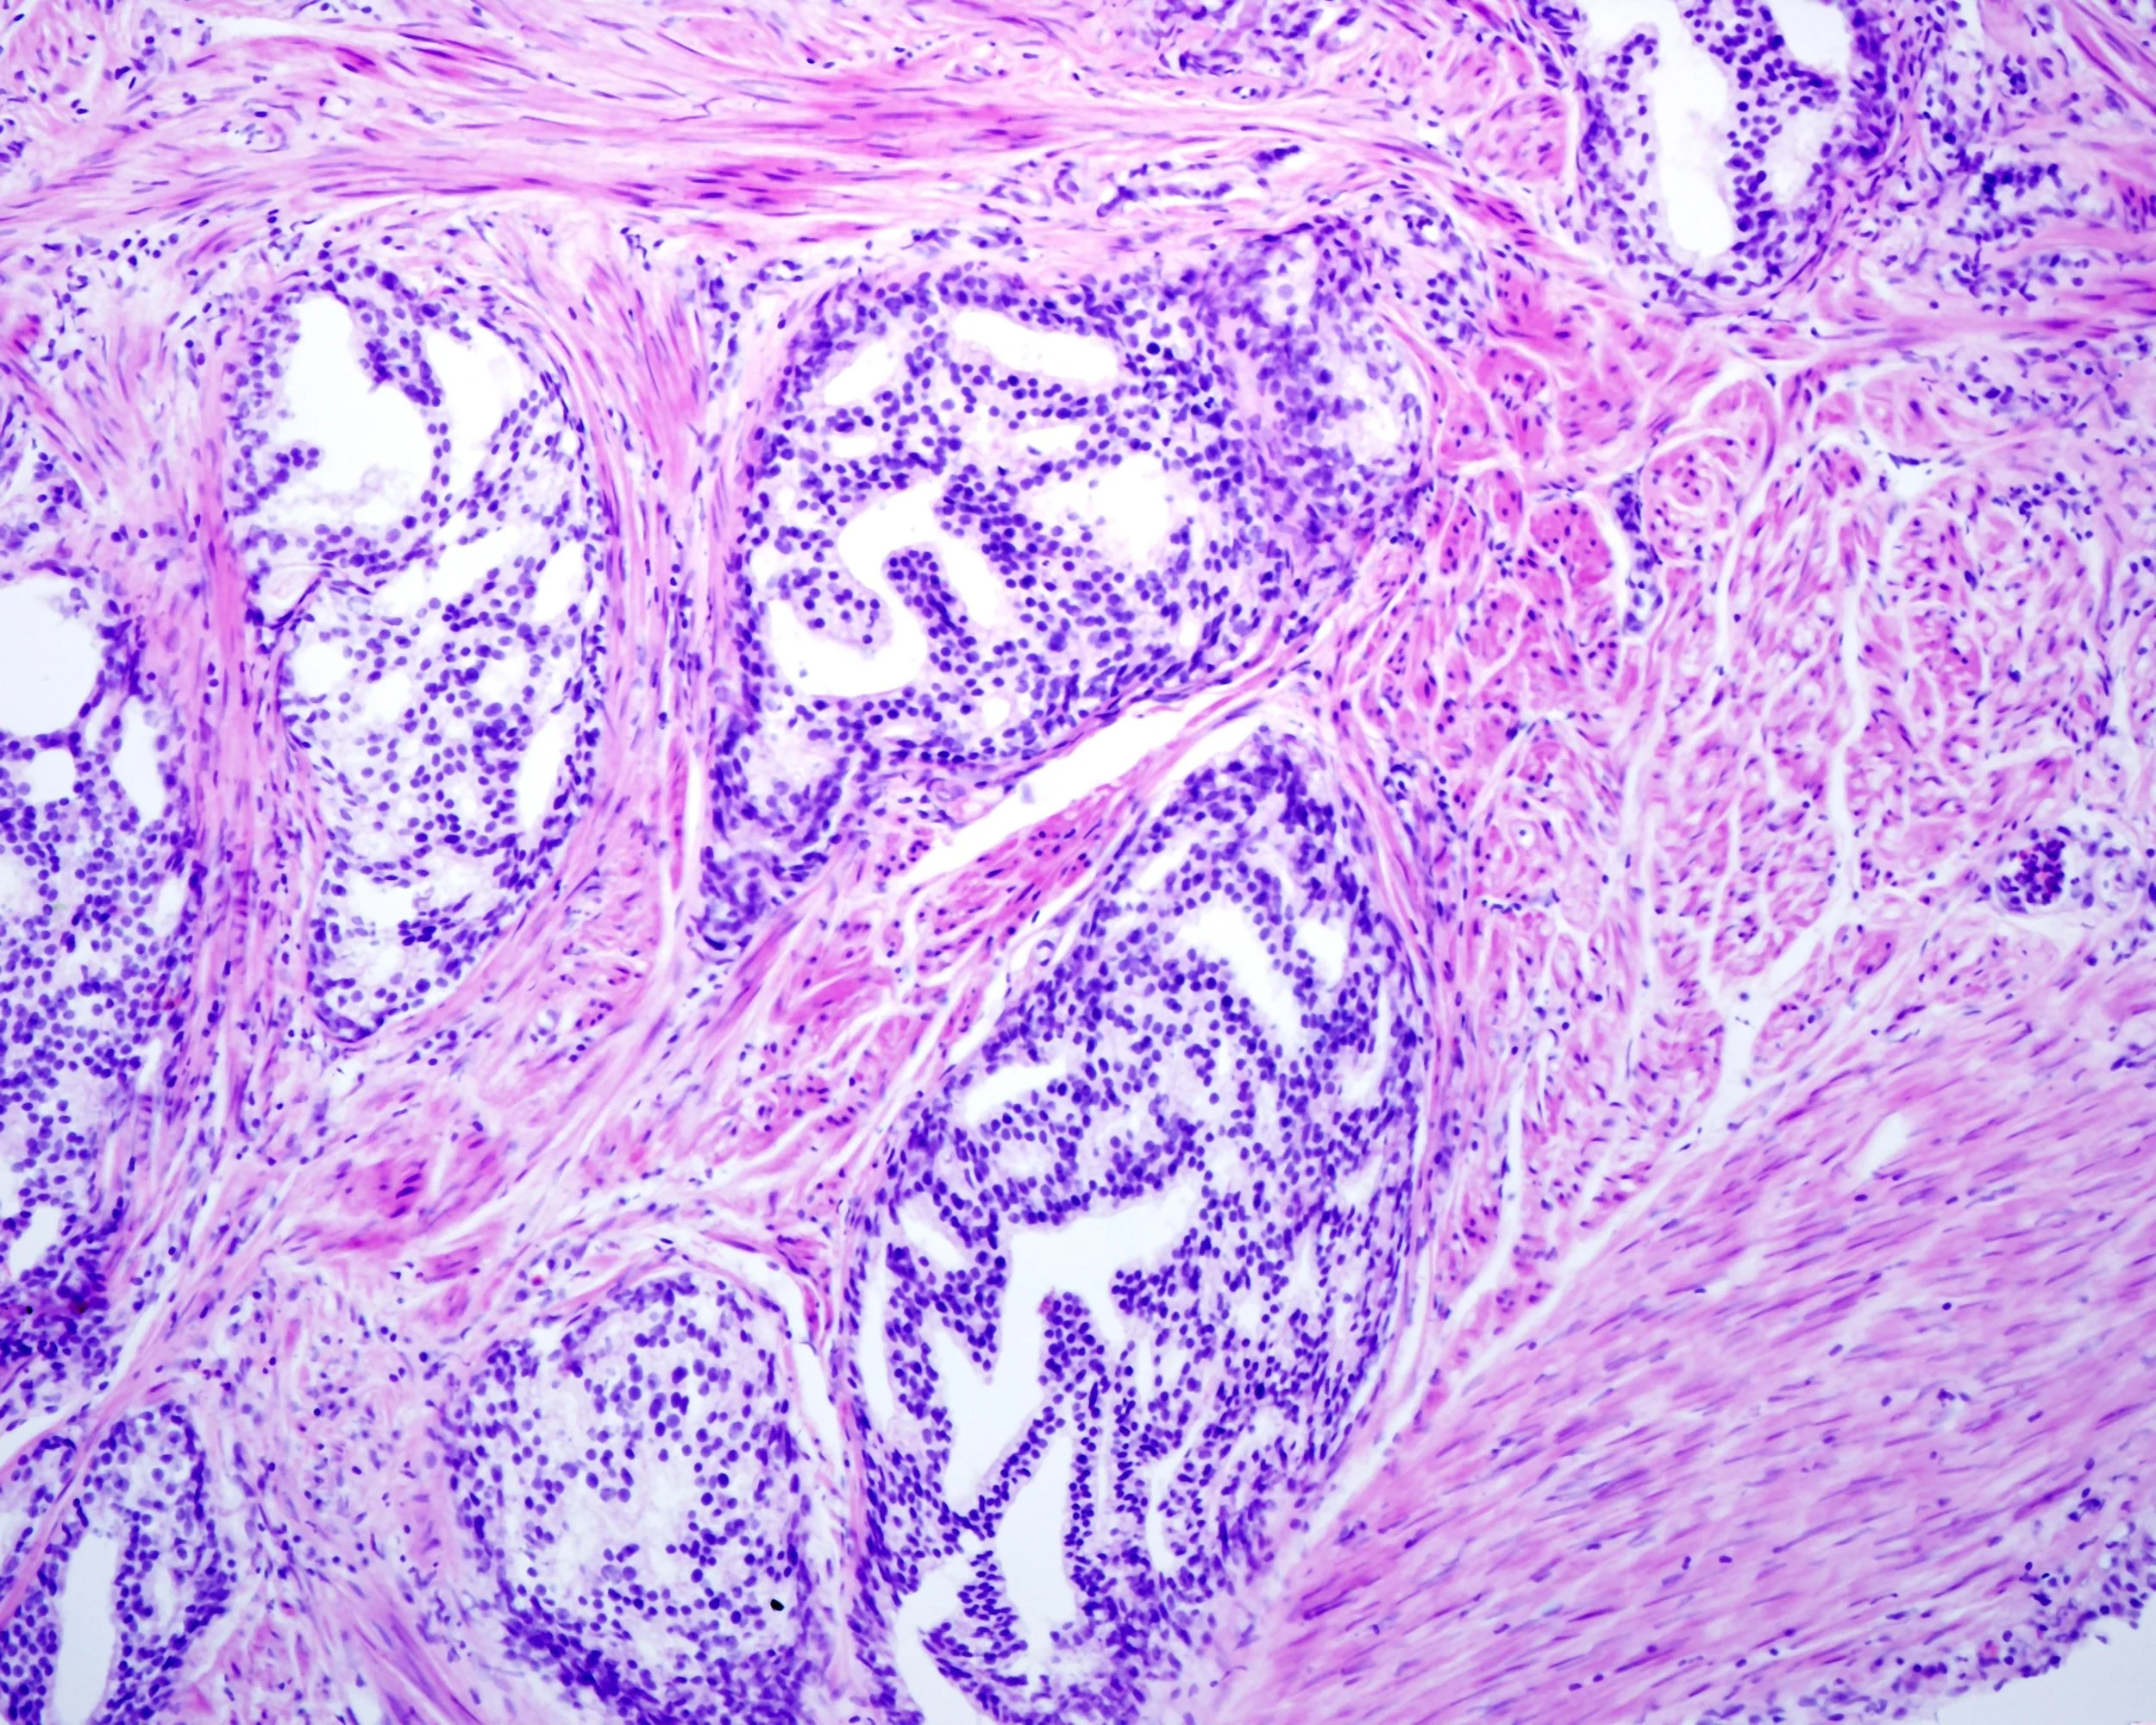

Cribriform morphology refers to a histologic pattern where cancerous glands form sieve-like or perforated structures. This architecture is often found in association with higher-grade prostate cancer and signals a higher risk of progression, metastasis, and mortality.

The clinical importance of cribriform morphology is well-documented. Research consistently demonstrates that its presence is strongly associated with worse outcomes, independent of other prognostic indicators such as Gleason score or PSA levels (1,2). As a result, its detection is becoming an essential criterion in guiding personalized treatment decisions, including the choice between active surveillance and more aggressive interventions.